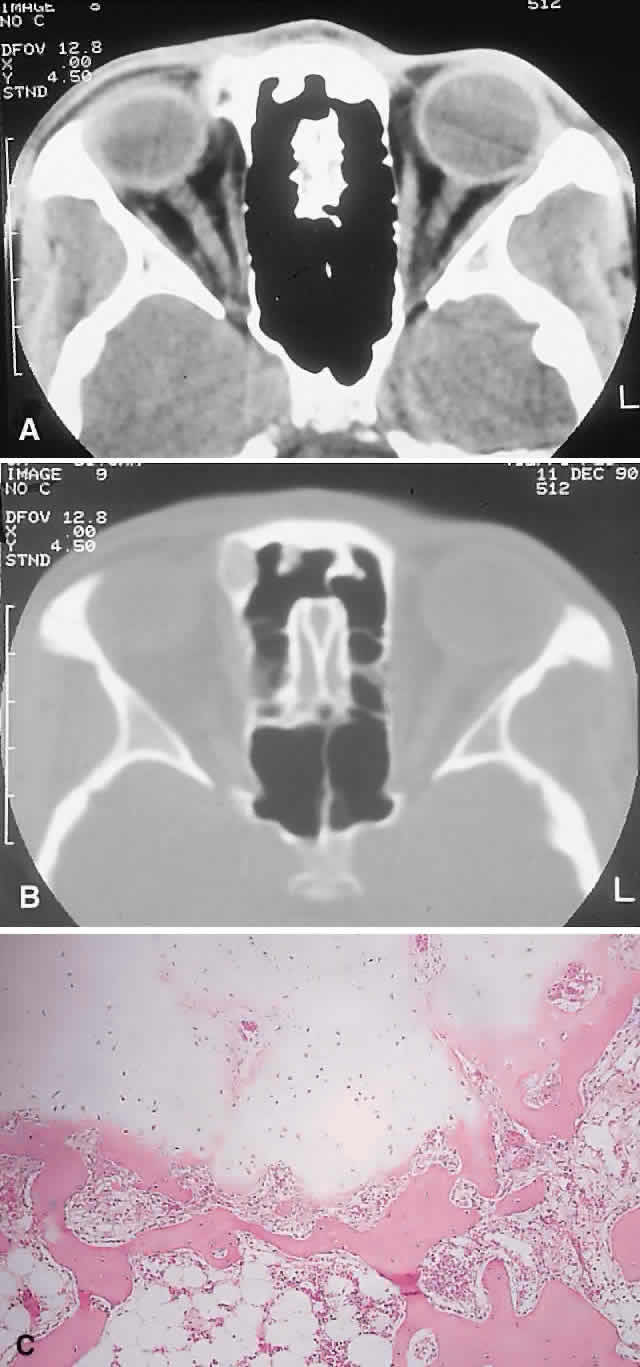

IMAGING. ABCs occurring in long bones have a characteristic uni- or multilocular expansile appearance. However, the radiology in the orbital bones is not specific and consists of destruction or expansion (Fig. 6). If expansile, the mass may have a thin cortical margin, but this is often absent as a consequence of erosion through to periorbita or dura. The central area is inhomogeneous, shows patchy enhancement, and can have multiple fluid levels, particularly in the more mature lesions.85,88 MRI may demonstrate recent hemorrhage in cases with an acute onset.

Fig. 6. An 11-year-old girl with a past history of acute lymphoid leukemia presented with decreasing left vision and proptosis. She had a left best corrected vision of 20/30, a relative afferent pupillary defect, and 2 mm of proptosis. A. CT demonstrated a destructive heterogeneous mass arising in the posterior ethmoid and sphenoid sinuses and involving the left orbital apex. A subtotal removal of the mass was achieved through a frontal craniotomy and orbitotomy. B. Histology showed a fibrous stroma containing giant cells, lymphocytes, and trabeculae of osteoid and bone (hematoxylin-eosin, × 20). There were also areas with giant cells, hemosiderin-laden macrophages, and small foci of aneurysmal sinusoids, leading to a diagnosis of solid aneurysmal bone cyst. There was no evidence of recurrence at follow-up 6 years later. C. Histology from another patient with aneurysmal bone cyst shows a typical cavernous, blood-filled space lacking endothelial lining, pericytes, or smooth muscle (hematoxylin-eosin, × 20). (A from Rootman J: Diseases of the Orbit: A Multidisciplinary Approach, p 373. Philadelphia: JB Lippincott, 1988.)

HISTOPATHOLOGY. The gross specimen almost always consists of curettings of reddish-brown tissue with a texture that varies from friable to fibrous or gritty. More solid lesions may yield softer, pink to gray-white tissue. If larger samples are available, one may see honeycombed areas of serosanguineous or blood-filled cavitation.18,40 The cardinal microscopic features are cavernous blood-filled spaces that lack endothelial lining, pericytes, or smooth muscle. These spaces are bounded by a fibrous stroma that contains giant cells, hemosiderin-laden macrophages, lymphocytes, and trabeculae of osteoid and bone. The osteoid may lack osteoblastic rimming and may seem to arise from the stroma in a metaplastic fashion. Degenerating chondromyxoid areas may surround the osteoid and can display partial calcification.18,40

In 1983, Sanerkin and coworkers90 described a solid variant of ABC in which the aneurysmal sinusoids were either seen only in small foci or were absent. We have seen two cases that fit this histologic description. It is evident that this picture, apart from the chondromyxoid and sinusoidal foci, may bear a close resemblance to giant cell granuloma.